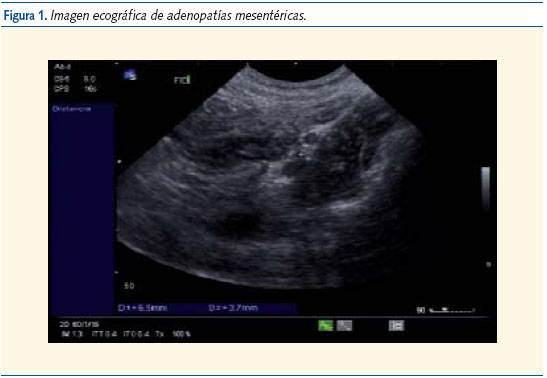

Evolución: durante su observación en urgencias presenta 4 vómitos y tendencia al sueño; se mantiene afebril en todo momento. Se le realiza una ecografía abdominal (figuras 1, 2 y 3) en la que se observa una invaginación ileo-ileal y es remitido al servicio de cirugía pediátrica del hospital de referencia, donde se repite la ecografía. No se encuentran entonces signos de dicha invaginación pero sí varias adenopatías mesentéricas. El paciente permaneció en observación 24 horas y fue dado de alta sin complicaciones.

La etiología de la invaginación intestinal es desconocida en un 80-90% de los casos. Se postula que un probable origen de esta patología se encontraría en una inflamación que acontece en las placas de Peyer y que actuaría como estímulo del peristaltismo intestinal para intentar expulsar la masa, produciendo la invaginación. Basándose en esta teoría, en algunos casos se han observado puntos que actúan de guía de la invaginación, tales como muñones apendiculares, pólipos, adenopatías mesentéricas (bastante frecuentes en el transcurso de las infecciones virales gastrointestinales)2 e incluso, aunque de manera extraordinaria, hematomas intramurales, como los presentes en algunos casos de púrpura Schönlein-Henoch3.